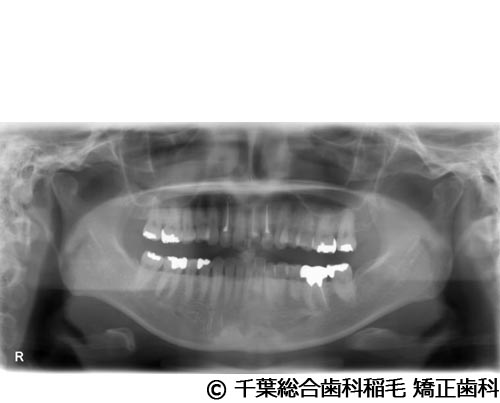

【症例4】上顎前歯1本インプラント埋入手術

- 治療前

- 治療後

- 治療名

- 上顎前歯1本インプラント埋入手術

- 費用

- 600,000円(税込)

- 期間

- 11ヵ月

治療内容

患者様の症状

前歯の色味が気になりご来院されました。

治療法

根っこが割れていたため抜歯となりました。

インプラント、ブリッジ、義歯それぞれのメリット、デメリットをお話させていただき、インプラントでの治療を選択されました。 -

治療結果

機能性、審美性ともに改善し、満足していただけました。

現在も定期検診で拝見させていただいています。